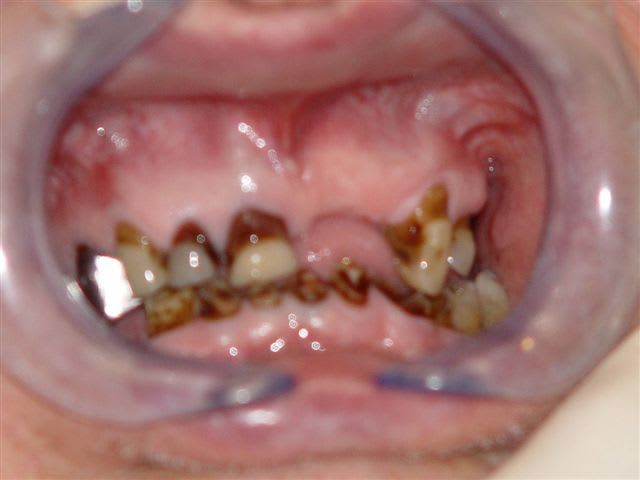

voilà dentiste57 quelques traitements dits globaux, effectivement, il y a eu refonte totale de la bouche avec les endos, la paro, l'occluso ect ... et ceci en 3 mois avec actes groupés sur un patient de 82 ans, j'aurais aimé lui mettre des implants, mais je n'ai pas eu le feu vert du cardiologue.

Avant traitement global w1rqna - Eugenol